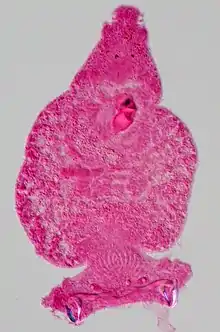

PAS

[13]Periodic acid-Schiff is a histology special stain used to mark carbohydrates (glycogen, glycoprotein, proteoglycans). PAS is commonly used on liver tissue where glycogen deposits are made which is done in efforts to distinguish different types of glycogen storage diseases. PAS is important because it can detect glycogen granules found in tumors of the ovaries and pancreas of the endocrine system, as well as in the bladder and kidneys of the renal system. Basement membranes can also show up in a PAS stain and can be important when diagnosing renal disease. Due to the high volume of carbohydrates within the cell wall of hyphae and yeast forms of fungi, the Periodic acid -Schiff stain can help locate these species inside tissue samples of the human body.